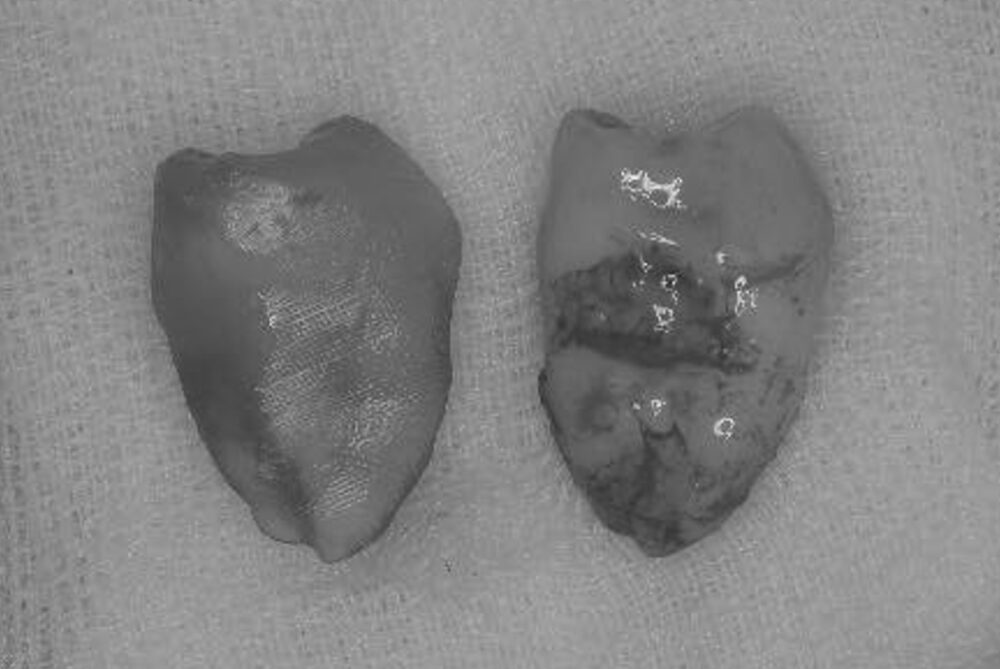

症例3

親知らずの抜歯

| 患者様データ | 40代 女性 |

| 来院時の主訴 | 「左側奥歯で噛むと痛い。」 |

| 医院の診断 | 歯根破折、慢性根尖性歯周炎 |

| 治療費 | 総額:330,000円(税抜) 【内訳】 歯牙移植150,000円、ファイバーポストコア20,000円、ダイレクトボンディング80,000円×2 |

| リスクと副作用 | ①根管治療歯は長期的には破折するリスク ②長期的なメインテナンスが必要 ③歯根の外部吸収 |

抜歯が必要になった際に余っている親知らずがあれば移植歯として利用することができます。 術前に撮影したCT画像から3Dプリンターを用いて親知らずのレプリカを作製することで、親知らずが乾燥することを防ぎ、成功率が上がるよう努力しています。 |